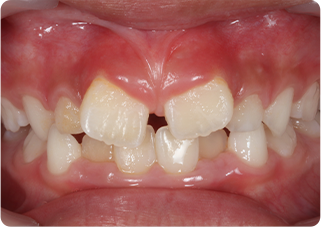

上唇小帯切除症例

術前

術後

| 主訴 | 上の前歯のすきっ歯が気になる |

|---|---|

| 治療期間/回数 | 1ヵ月、3回 |

| 価格(税込) | 保険適応 |

| リスク・副作用 | 出血、術後疼痛の可能性 |

| ポイント | 上唇小帯の付着異常により、正中離開が起きていた。上唇小帯を電気メスで切除した結果、歯を正中に寄せることが出来た。 |